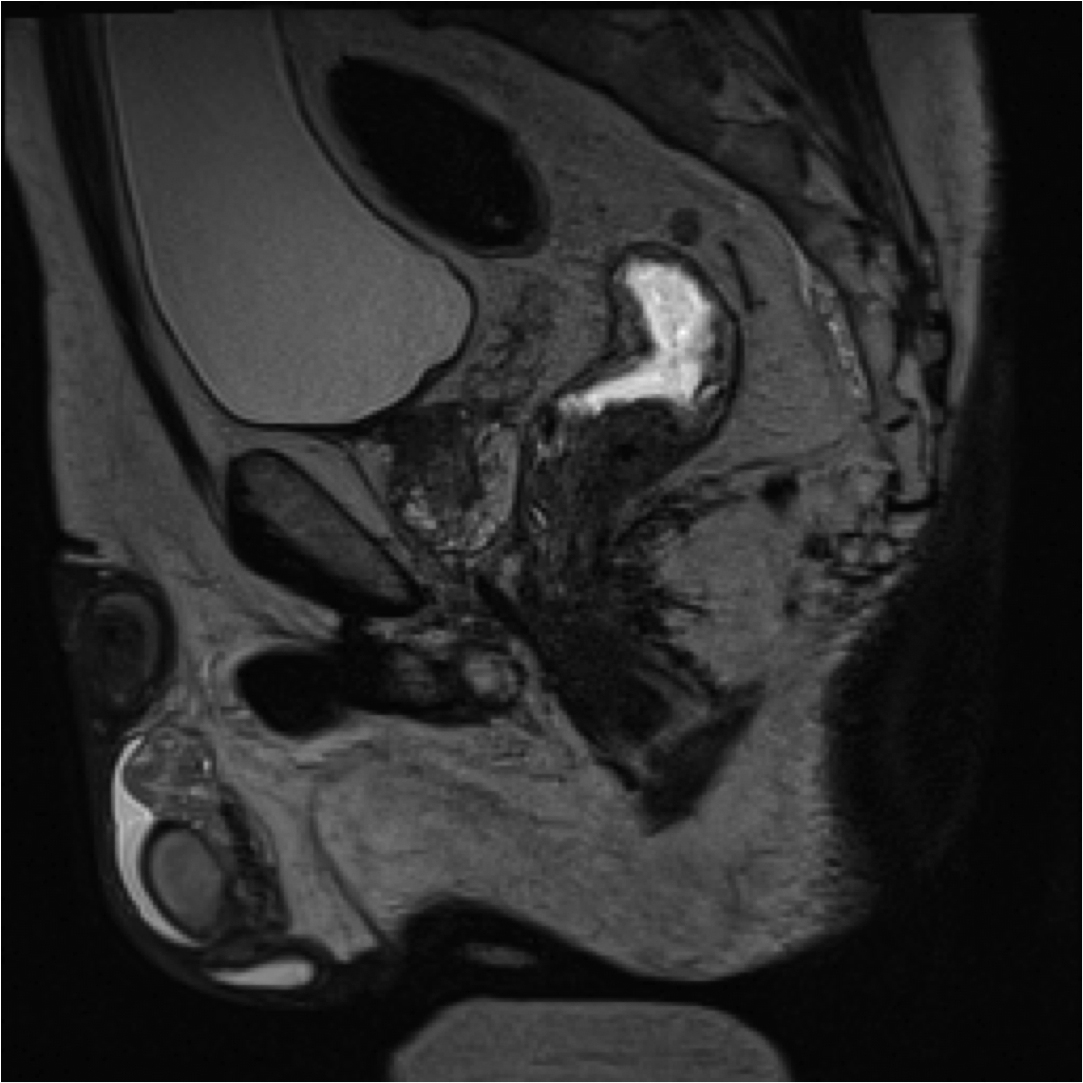

Fig1. Pacient cu neoplasm rectal stadiul IIIC (T3; N2; M0) confirmat bioptic, adenocarcinom mixt G2

a-d imagini T2 ponderate în plan sagital, oblic axial și oblic coronal – masă tisulară dezvoltată superior de joncțiunea anorectală, lateral dreapta, cu minimă extensie la nivelul grăsimii mezorectale și limfoganglioni mezorectali cu diametru de până la 10 mm;

e,f) restricție de difuzie la nivelul tumorii rectale și a doi ganglioni mezorectali

g,h,i) priză de contrast moderată la nivelul tumorii rectale și al ganglionilor mezorectali

j) reconstrucții curbe în planul adevărat al rectului, cu evidențiere mai bună a fasciei mezorectale